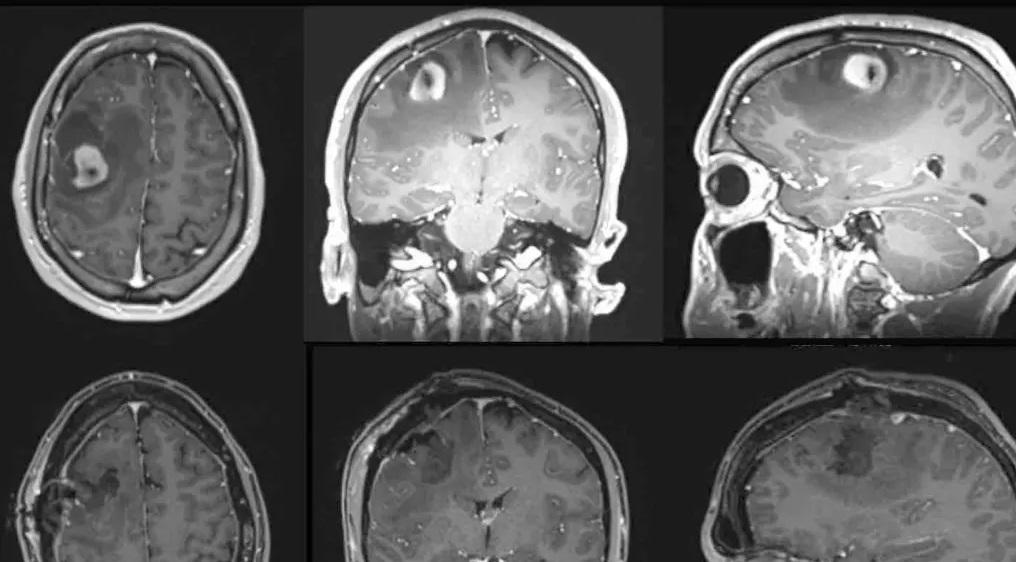

霍士新聞報道,諾倫某天注意到左邊身體不受控,尤其手部動作笨拙,影響到彈結他,其後確診患上右側前額葉腫瘤。邁亞密大學腦腫瘤醫生科莫塔爾(Dr. Ricardo Komotar)表示,諾倫須接受手術確認腫瘤類型及治療方式等,如果在清醒情況下一邊彈結他一邊動手術,可幫助醫生盡可能切除整處腫瘤的同時,更好地評估並確保他手部的靈活性。

科莫塔爾解釋,當腫瘤涉及或靠近大腦關鍵部位(即控制說話或理解語言,或活動能力的部位)時,如果進行清醒手術,醫療團隊透過持續監測病人,能確認是否破壞大腦功能,但若病人在麻醉狀態下,就無法獲得即時回應,「手術實際上會更加危險,因為你(醫生)可能切除一處涉及正常大腦功能的腫瘤,並在不知情下造成實質傷害」。

事實是,手術期間,團隊發現諾倫的腫瘤與控制手部動作的大腦部位有所接觸,幸好醫生最終能成功切除,並沒影響病人的手部運動能力。